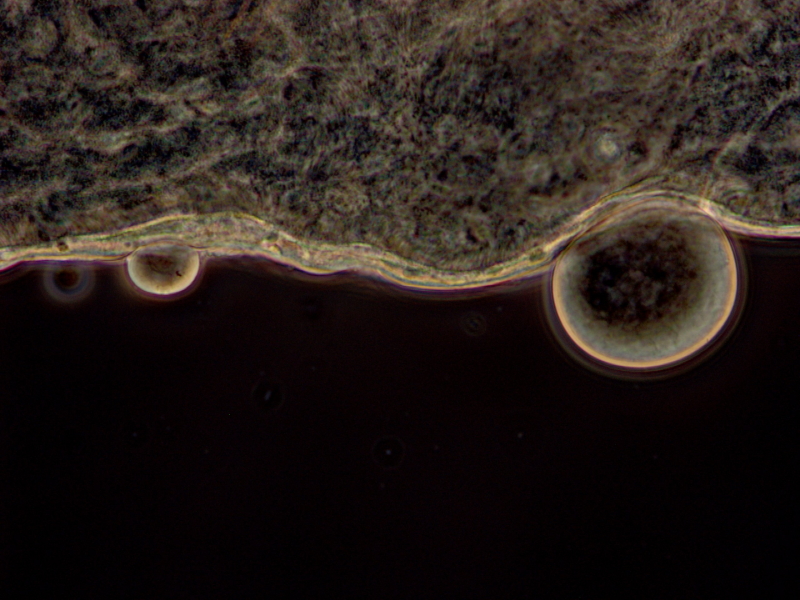

Oocyst -- non-infectious stage of malaria -- of Plasmodium yoelii (rodent malaria) attach to the wall of a mosquito midgut. Credit: Krijn Paaijmans, Universitat de Barcelona